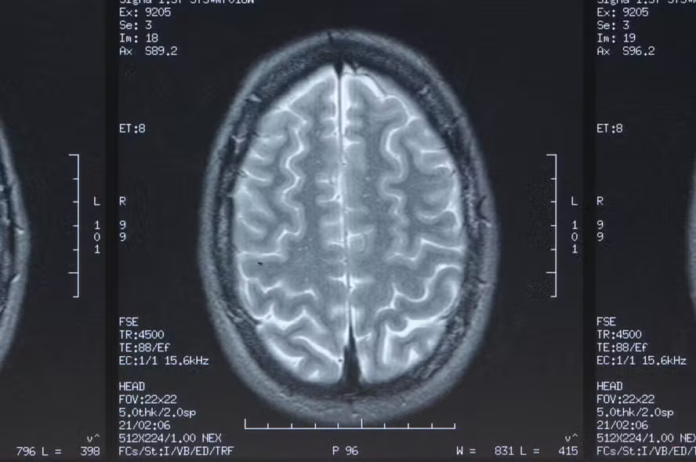

Para encontrar as evidências, os pesquisadores escanearam o cérebro de um homem de 26 anos 40 vezes no período de 30 dias. Os exames de ressonância magnética foram realizados às 7h e às 20h. Na manhã, o grupo de três hormônios estão em seu nível mais alto, enquanto à noite, estão no mais baixo.

São afetadas a espessura do córtex (a camada mais externa do cérebro), especialmente os córtices occipital e parietal foram as que mais encolhem e a matéria cinzenta (composta pelos neurônios e as conexões entre eles), que perde 0,6% do seu tamanho original.

Além delas, outras regiões mais distantes do cérebro, como o cerebelo (responsável coordenação motora, o equilíbrio e o controle do tônus muscular), tronco cerebral (mensageiro entre cérebro e corpo) e partes do hipocampo (armazenamento de memórias), também apresentaram diferenças.